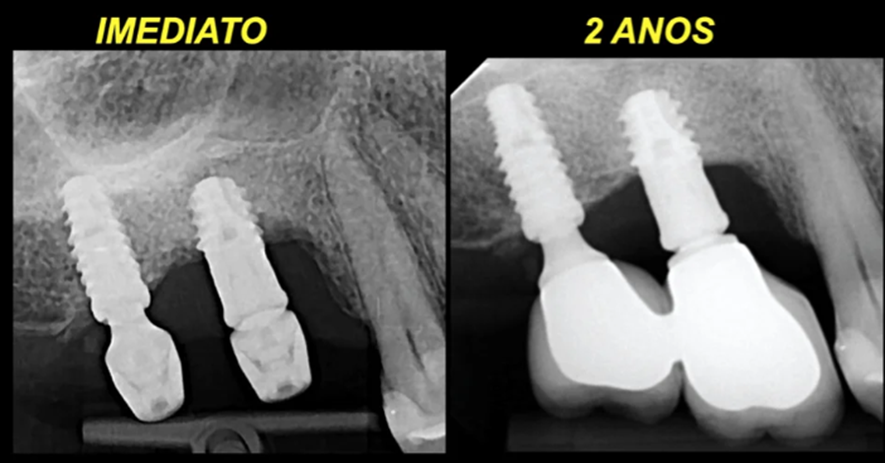

Este caso foi solucionado através da realização de uma implantoplastia (remoção e alisamento, com brocas de alta rotação e borrachas de polimento, das espiras contaminadas e que sofreram perdas ósseas). Após dois anos de controle, observou-se que a perda óssea cessou e a saúde peri-implantar foi reestabelecida. As figuras 2 a 4 ilustram a técnica de implantoplastia.

Ao analisarmos este caso, observamos que no implante 17 (onde não houve peri-implantite), o pilar utilizado tinha 1,5 mm de altura. A hipótese que podemos acreditar é a de que esta cinta mais alta de 1,5 mm do implante 17 favoreceu a adaptação dos tecidos moles, com respeito ao espaço biológico peri-implantar. Já o pilar de 0,8 mm, colocado no implante 16, comprimiu o espaço biológico e gerou uma resposta destrutiva do paciente, com uma reabsorção óssea peri-implantar.

O fato mais curioso deste caso é que a implantoplastia possibilitou uma redução do diâmetro do implante na parte onde as espiras foram eliminadas. Desta forma, esta longa parte lisa funciona como um pilar longo e mais estreito, uma vez que não haverá formação óssea sobre esta superfície modificada pela implantoplastia. Na verdade, criou-se um ambiente favorável para a adaptação dos tecidos moles peri-implantares com respeito ao espaço biológico.